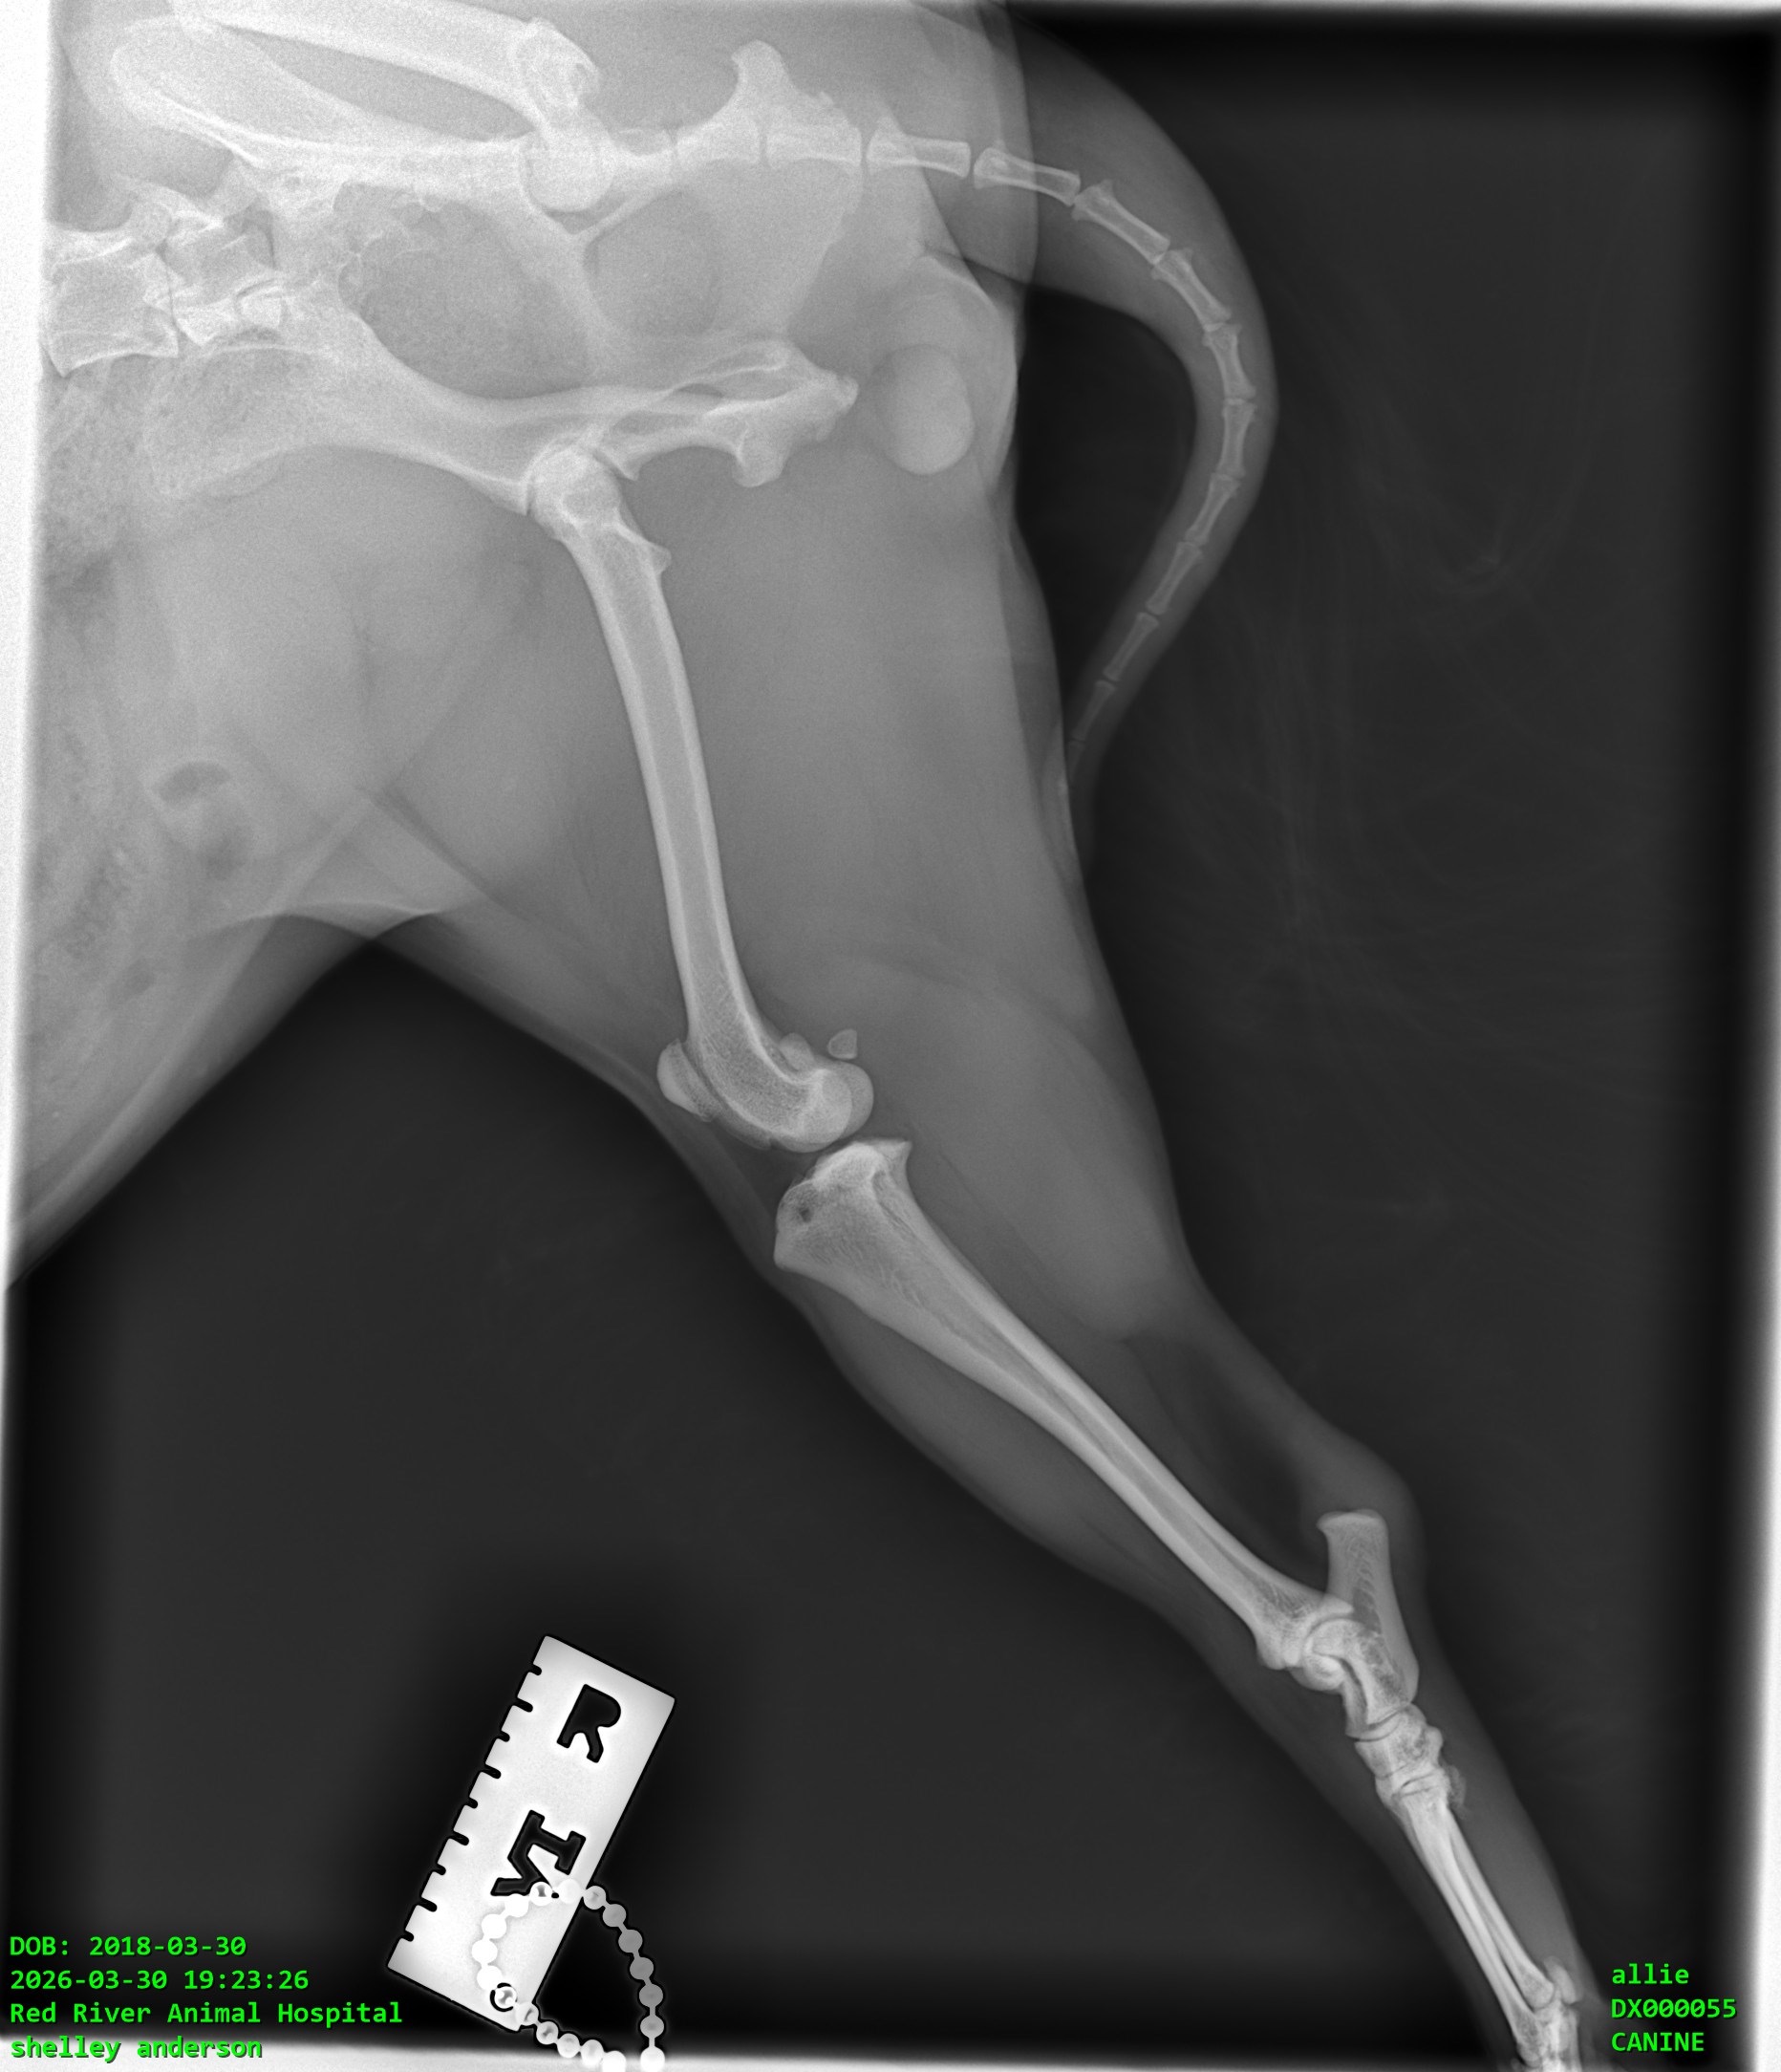

Allie is our 8-year-old Morkie, and she means absolutely everything to us, and especially to my mom. Allie is her whole world and goes everywhere with her. Recently, Allie was suddenly unable to put weight on her back leg. After taking her to the vet, we were told she has a torn ligament in her knee (CCL), which is very painful and requires surgery to properly fix.

Right now, she’s on pain medication and resting, but without surgery, there’s a risk of ongoing pain and long-term damage. We want to give her the best chance at a happy, comfortable life.

We were quoted between $5,000 and $5,500 for the surgery. If we don’t reach the full goal, the money will still go toward Allie’s care, like her medications, follow-up vet visits, rehabilitation, and possibly a more affordable surgical option or partial payment toward surgery. Nothing will go to waste, it will all be used for her treatment.